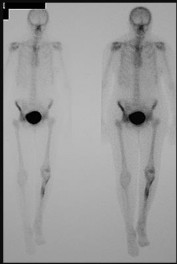

Figures 12a and 12b are a recent radiograph and a whole-body bone scan of an 81-year-old man who has hip pain and difficulty walking. His medical history is significant for obesity, hypertension, chronic kidney disease, and coronary artery disease. An examination demonstrates

moderate tenderness with passive range of motion of the left hip and an inability to actively flex the left hip against gravity. What is the best next step?

This patient has no known history of active malignancy. The radiograph shows a lesser trochanteric avulsion fracture (a fracture routinely associated with an underlying neoplasm). The bone scan reveals no other bone lesions. The femur fracture is statistically most likely to occur because of metastatic disease, but, without other evidence of metastasis, a primary bone sarcoma is possible, and biopsy is recommended before surgical fixation. Observation of this fracture, which is pathognomonic for neoplastic disease, is strongly discouraged.